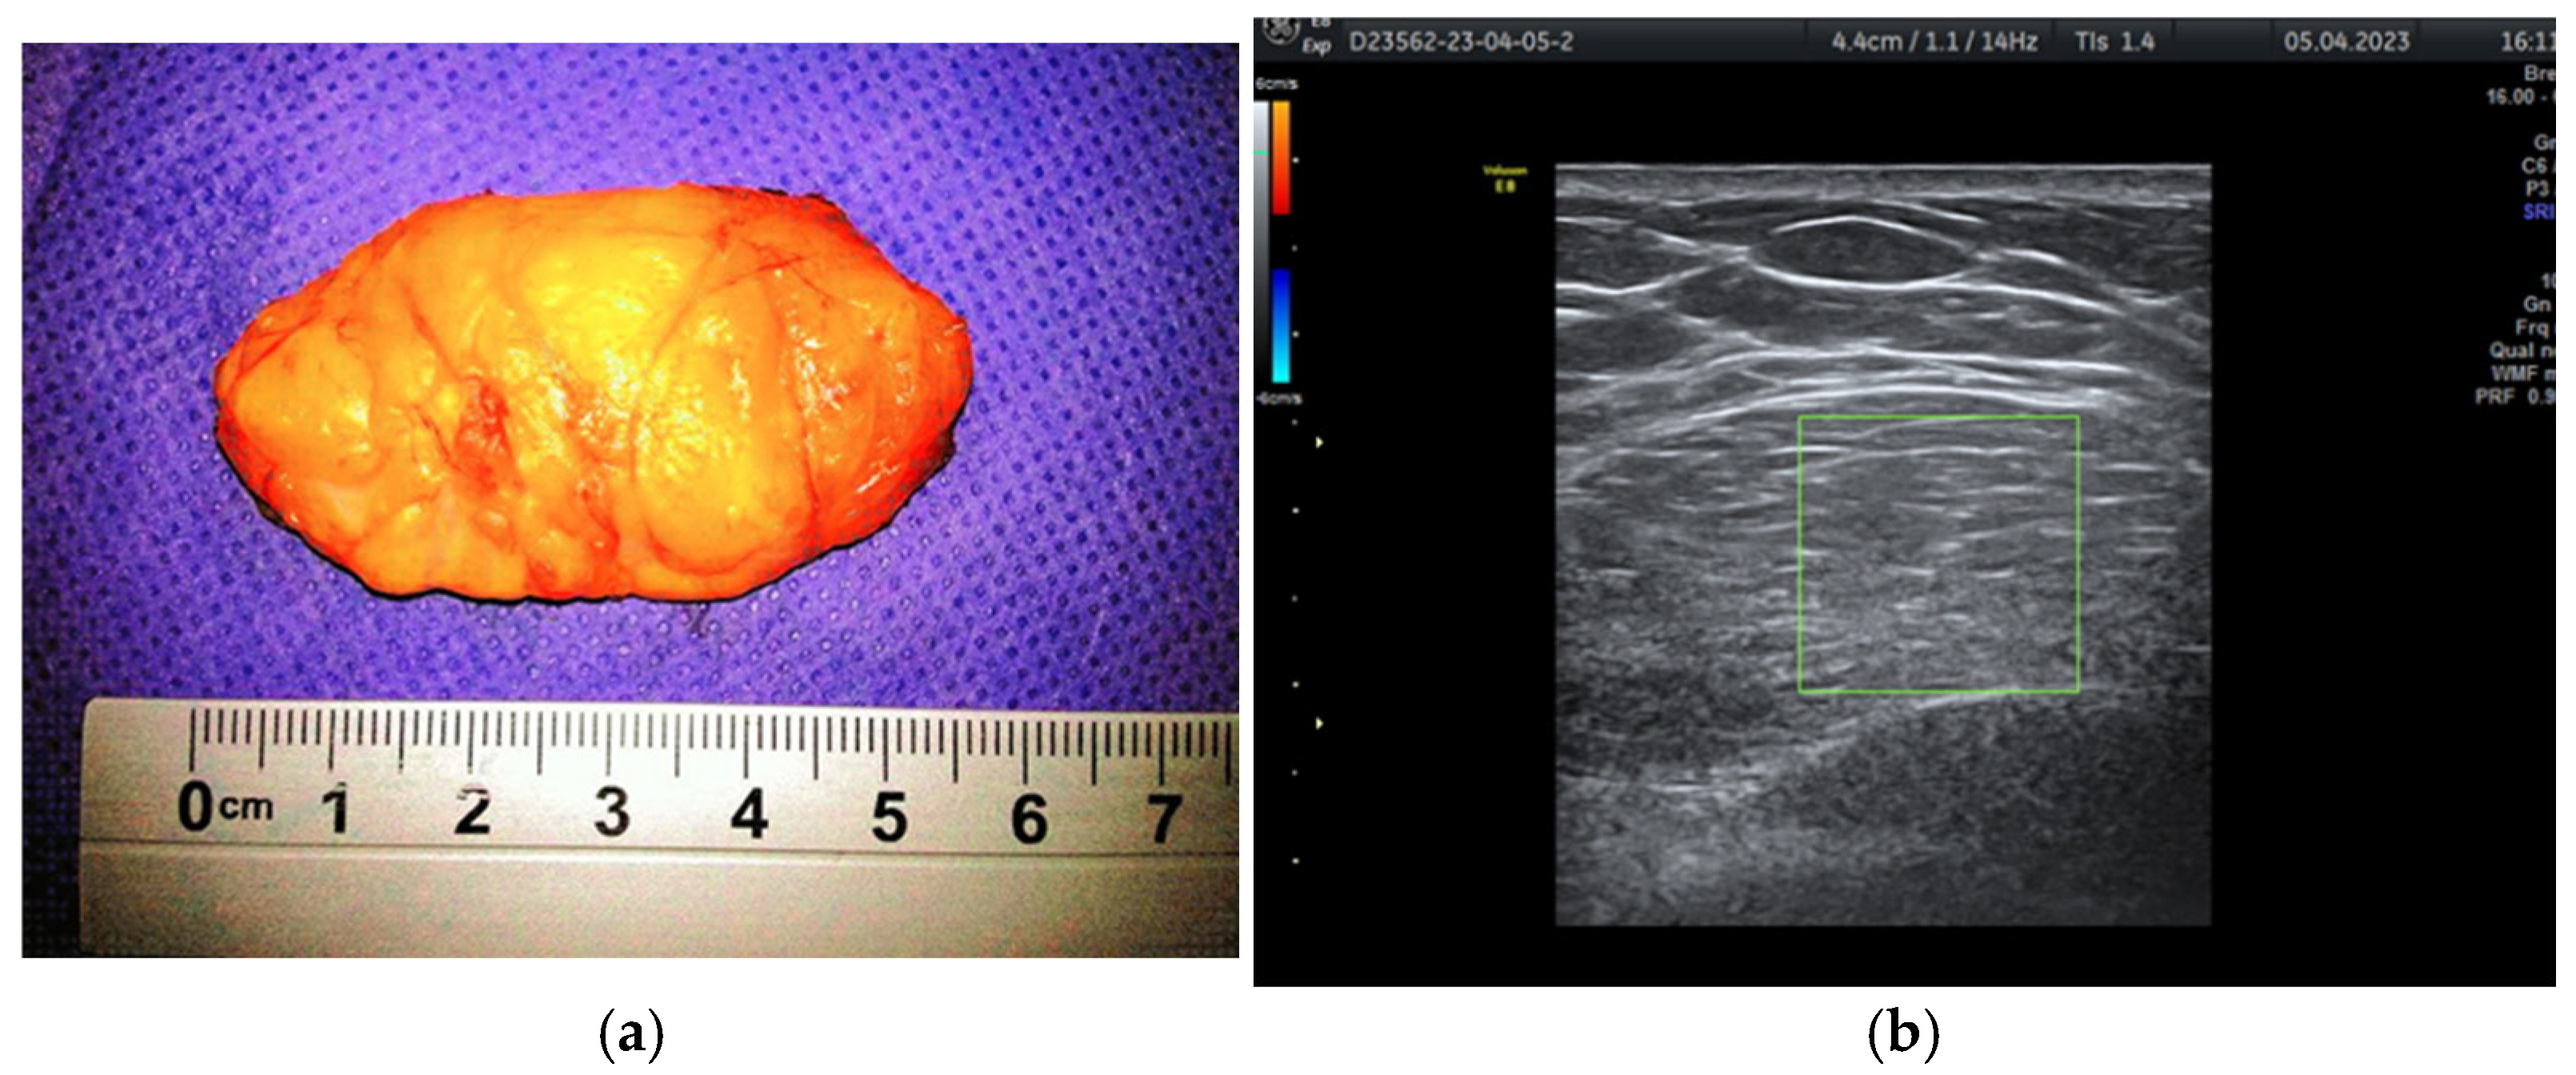

Figure 4. Breast lipoma in a 52-year-old woman (a) macroscopic pathological aspect; (b) ultrasound exam—hypoechoic aspect with thin striations.

During the study period, a case initially suspected to be a hamartoma on MRI, with peripheral vessel involvement and benign axillary adenopathy, was encountered. However, an ultrasound examination established the diagnosis of a 5 × 3 cm lipoma in a 52-year-old woman, despite the tumor’s rapid growth over the course of one year (Figure 4a,b). The lipoma consisted solely of homogeneous adipose tissue, appearing hypoechoic on the ultrasound exam, with few thin striations. This case is particularly significant as it highlights the diagnostic challenges associated with differentiating between breast hamartomas and lipomas, especially in instances where rapid tumor growth is observed over one year.